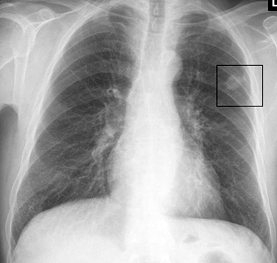

Диагностика рака легких с помощью рентгена, флюорографии и КТ

Рак легких является ведущей причиной смертности среди других видов рака. Причина в позднем обнаружении. Поэтому своевременной диагностике рака легких уделяется особое внимание. Несомненно, необходим комплексный подход к качественной и полной диагностике с использованием всех возможных методов исследования. Однако радиологические методы играют ключевую роль как в скрининге, так и в подтверждении диагноза. Например, флюорография чаще всего …